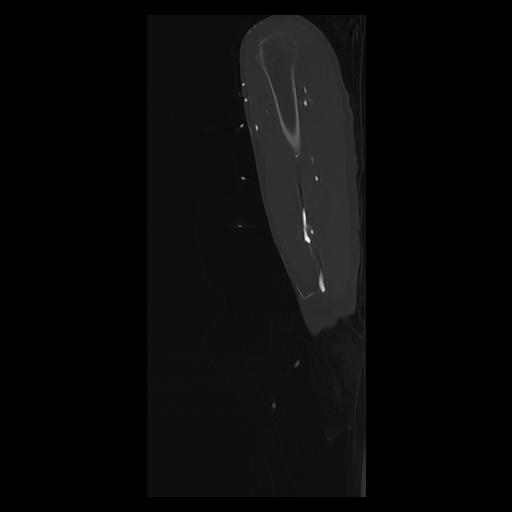

33 PULMON,CE,Sagittal,3.000,PULMON,Sagittal,